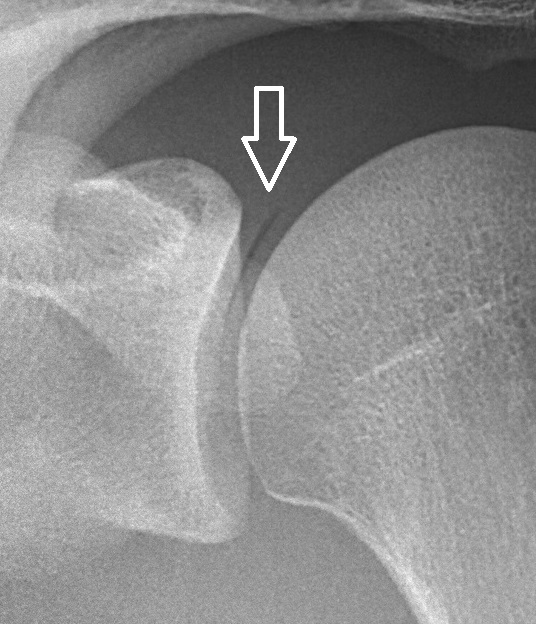

류마티스 관절염은 관절 주위를 둘러싸고 있는 활막이라는 조직의 염증으로 인해 발생하는 질환입니다.

이 질환은 활막이 존재하는 모든 관절, 즉 움직일 수 있는 거의 모든 관절에서 발생할 수 있습니다.